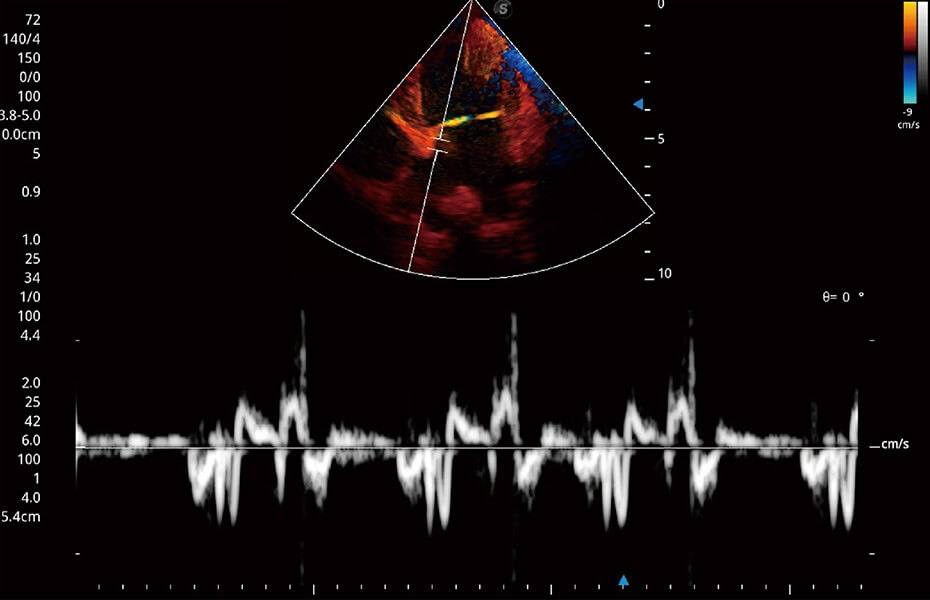

ProPet 60 作為一款高端臺式動物超聲設(shè)備,為動物醫(yī)生的日常診斷提供了一系列貼合動物臨床需求、解決臨床實(shí)際問題的高級成像功能。憑借全系列高清探頭,滿足醫(yī)生對腹部、心臟、生殖、淺表、肌骨等成像的所有需求,切實(shí)幫助您提升檢查效率,提高診斷信心。